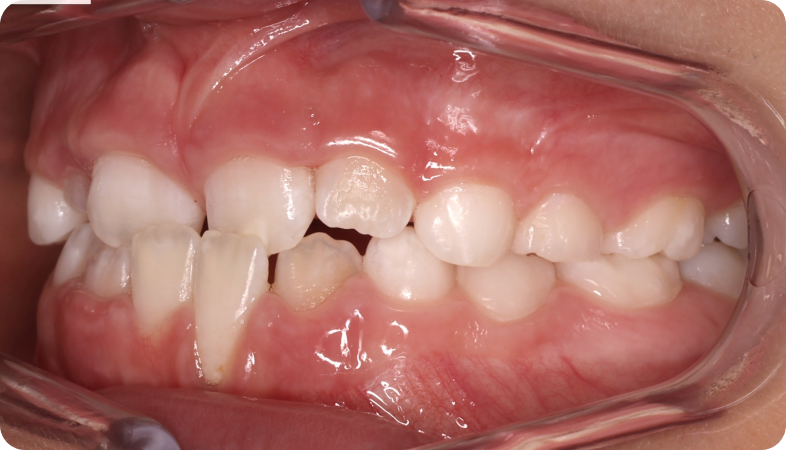

Cas cliniques